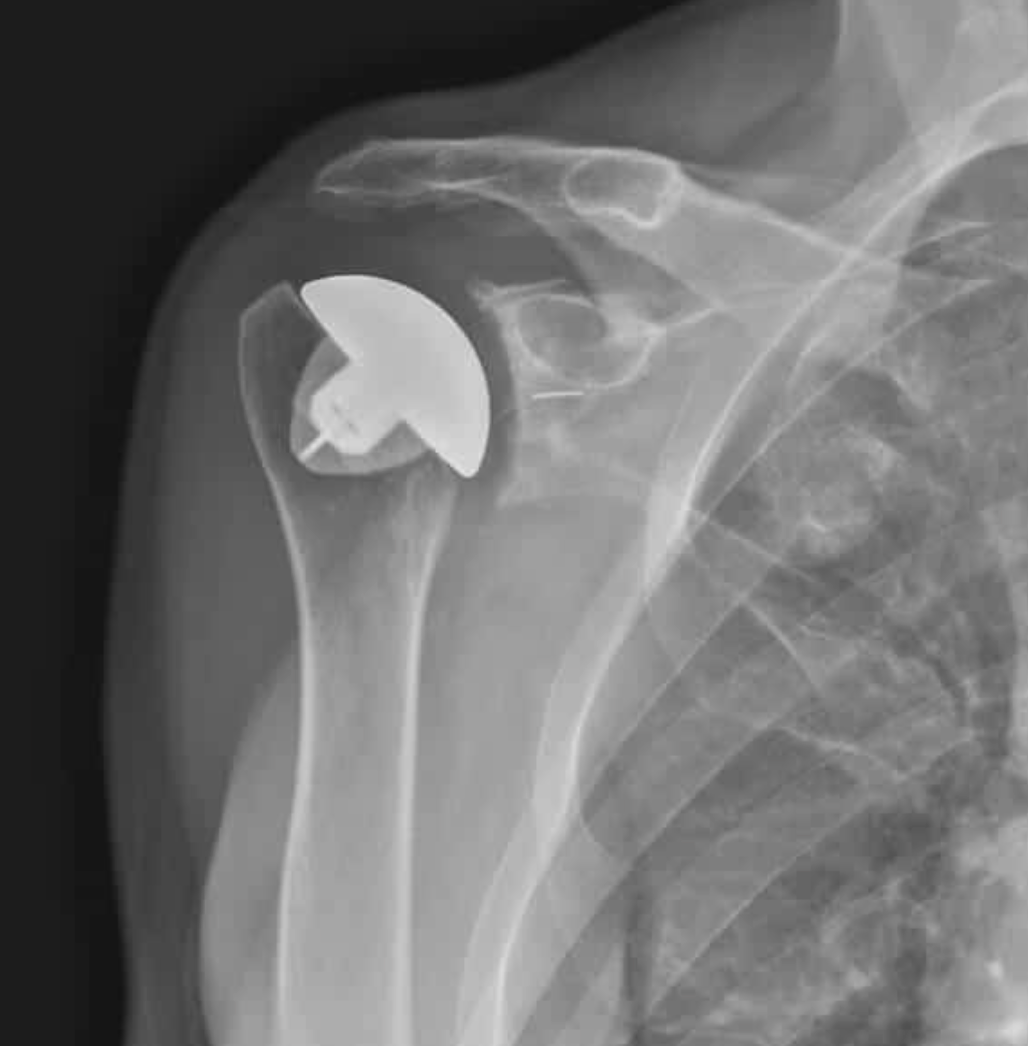

Reverse Total Shoulder Arthroplasty (RTSA):

- In RTSA, the normal ball-and-socket structure is switched: the ball is placed on the shoulder blade, and the socket is placed on the upper arm bone.[3][4][5]

- RTSA is designed for people with a torn or irreparable rotator cuff, severe shoulder arthritis, or major bone loss in the socket.

- It is often used for older adults, those with complex fractures, or those at risk for future rotator cuff problems.[1][2][6][10][7][11][12]

- RTSA does not rely on the rotator cuff for movement. Instead, the deltoid muscle (on the outside of your shoulder) helps lift your arm.[1][2][13][10][3][4][11]

- RTSA can provide reliable pain relief and improved ability to raise your arm overhead, especially if you had trouble lifting your arm before surgery.[8][14]

- Some patients may have slightly less rotation compared to ATSA, and RTSA may have a higher risk of certain complications if the rotator cuff is healthy.[13][6][14][9]

X-ray image of a shoulder with a reverse shoulder prosthesis